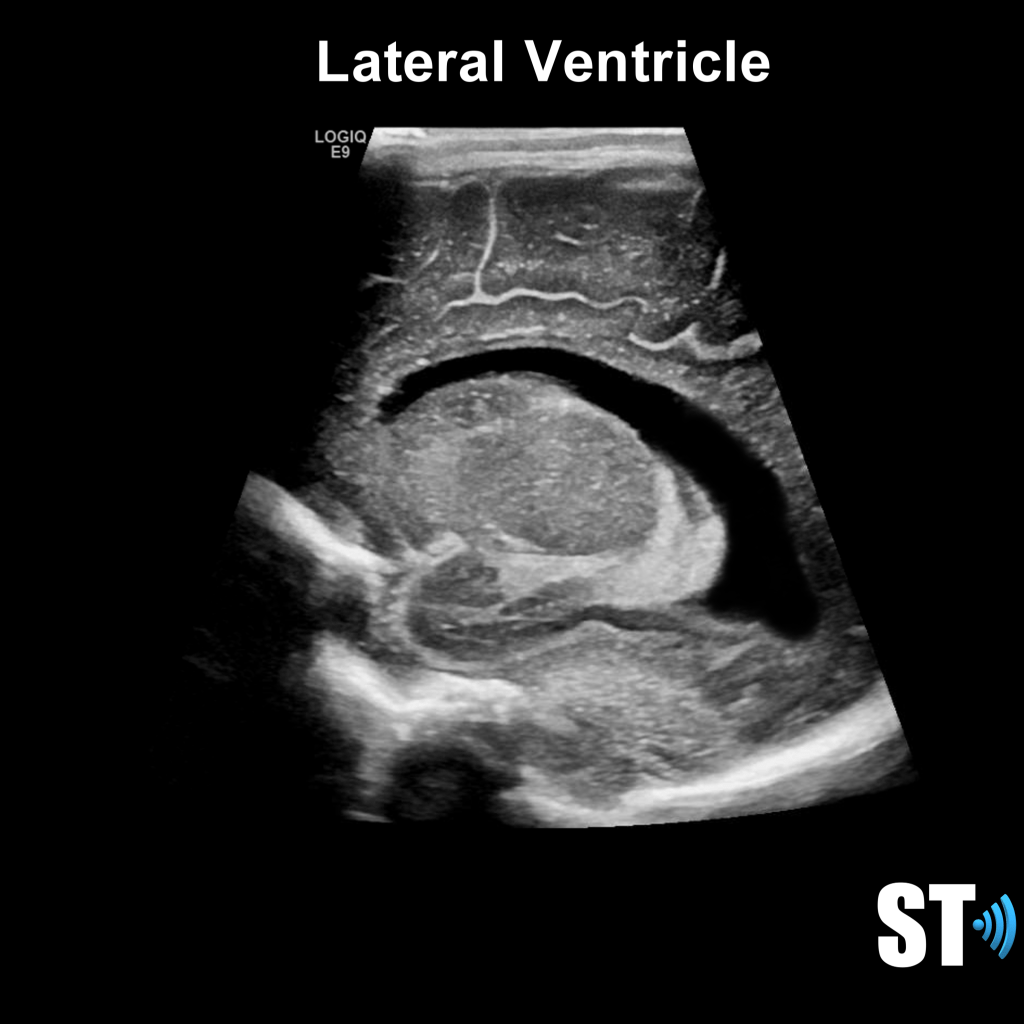

Ventricular System

The ventricular system is a series of chamber deep within the brain that collect and allow the flow of cerebrospinal fluid. The main components are the paired lateral, third and fourth ventricles.

Within each ventricle is the choroid plexus which is a network of cells that line the bodies of the lateral ventricles, the roof of the third ventricle and a little bit in the fourth ventricle. The choroid plexus creates the cerebrospinal fluid.